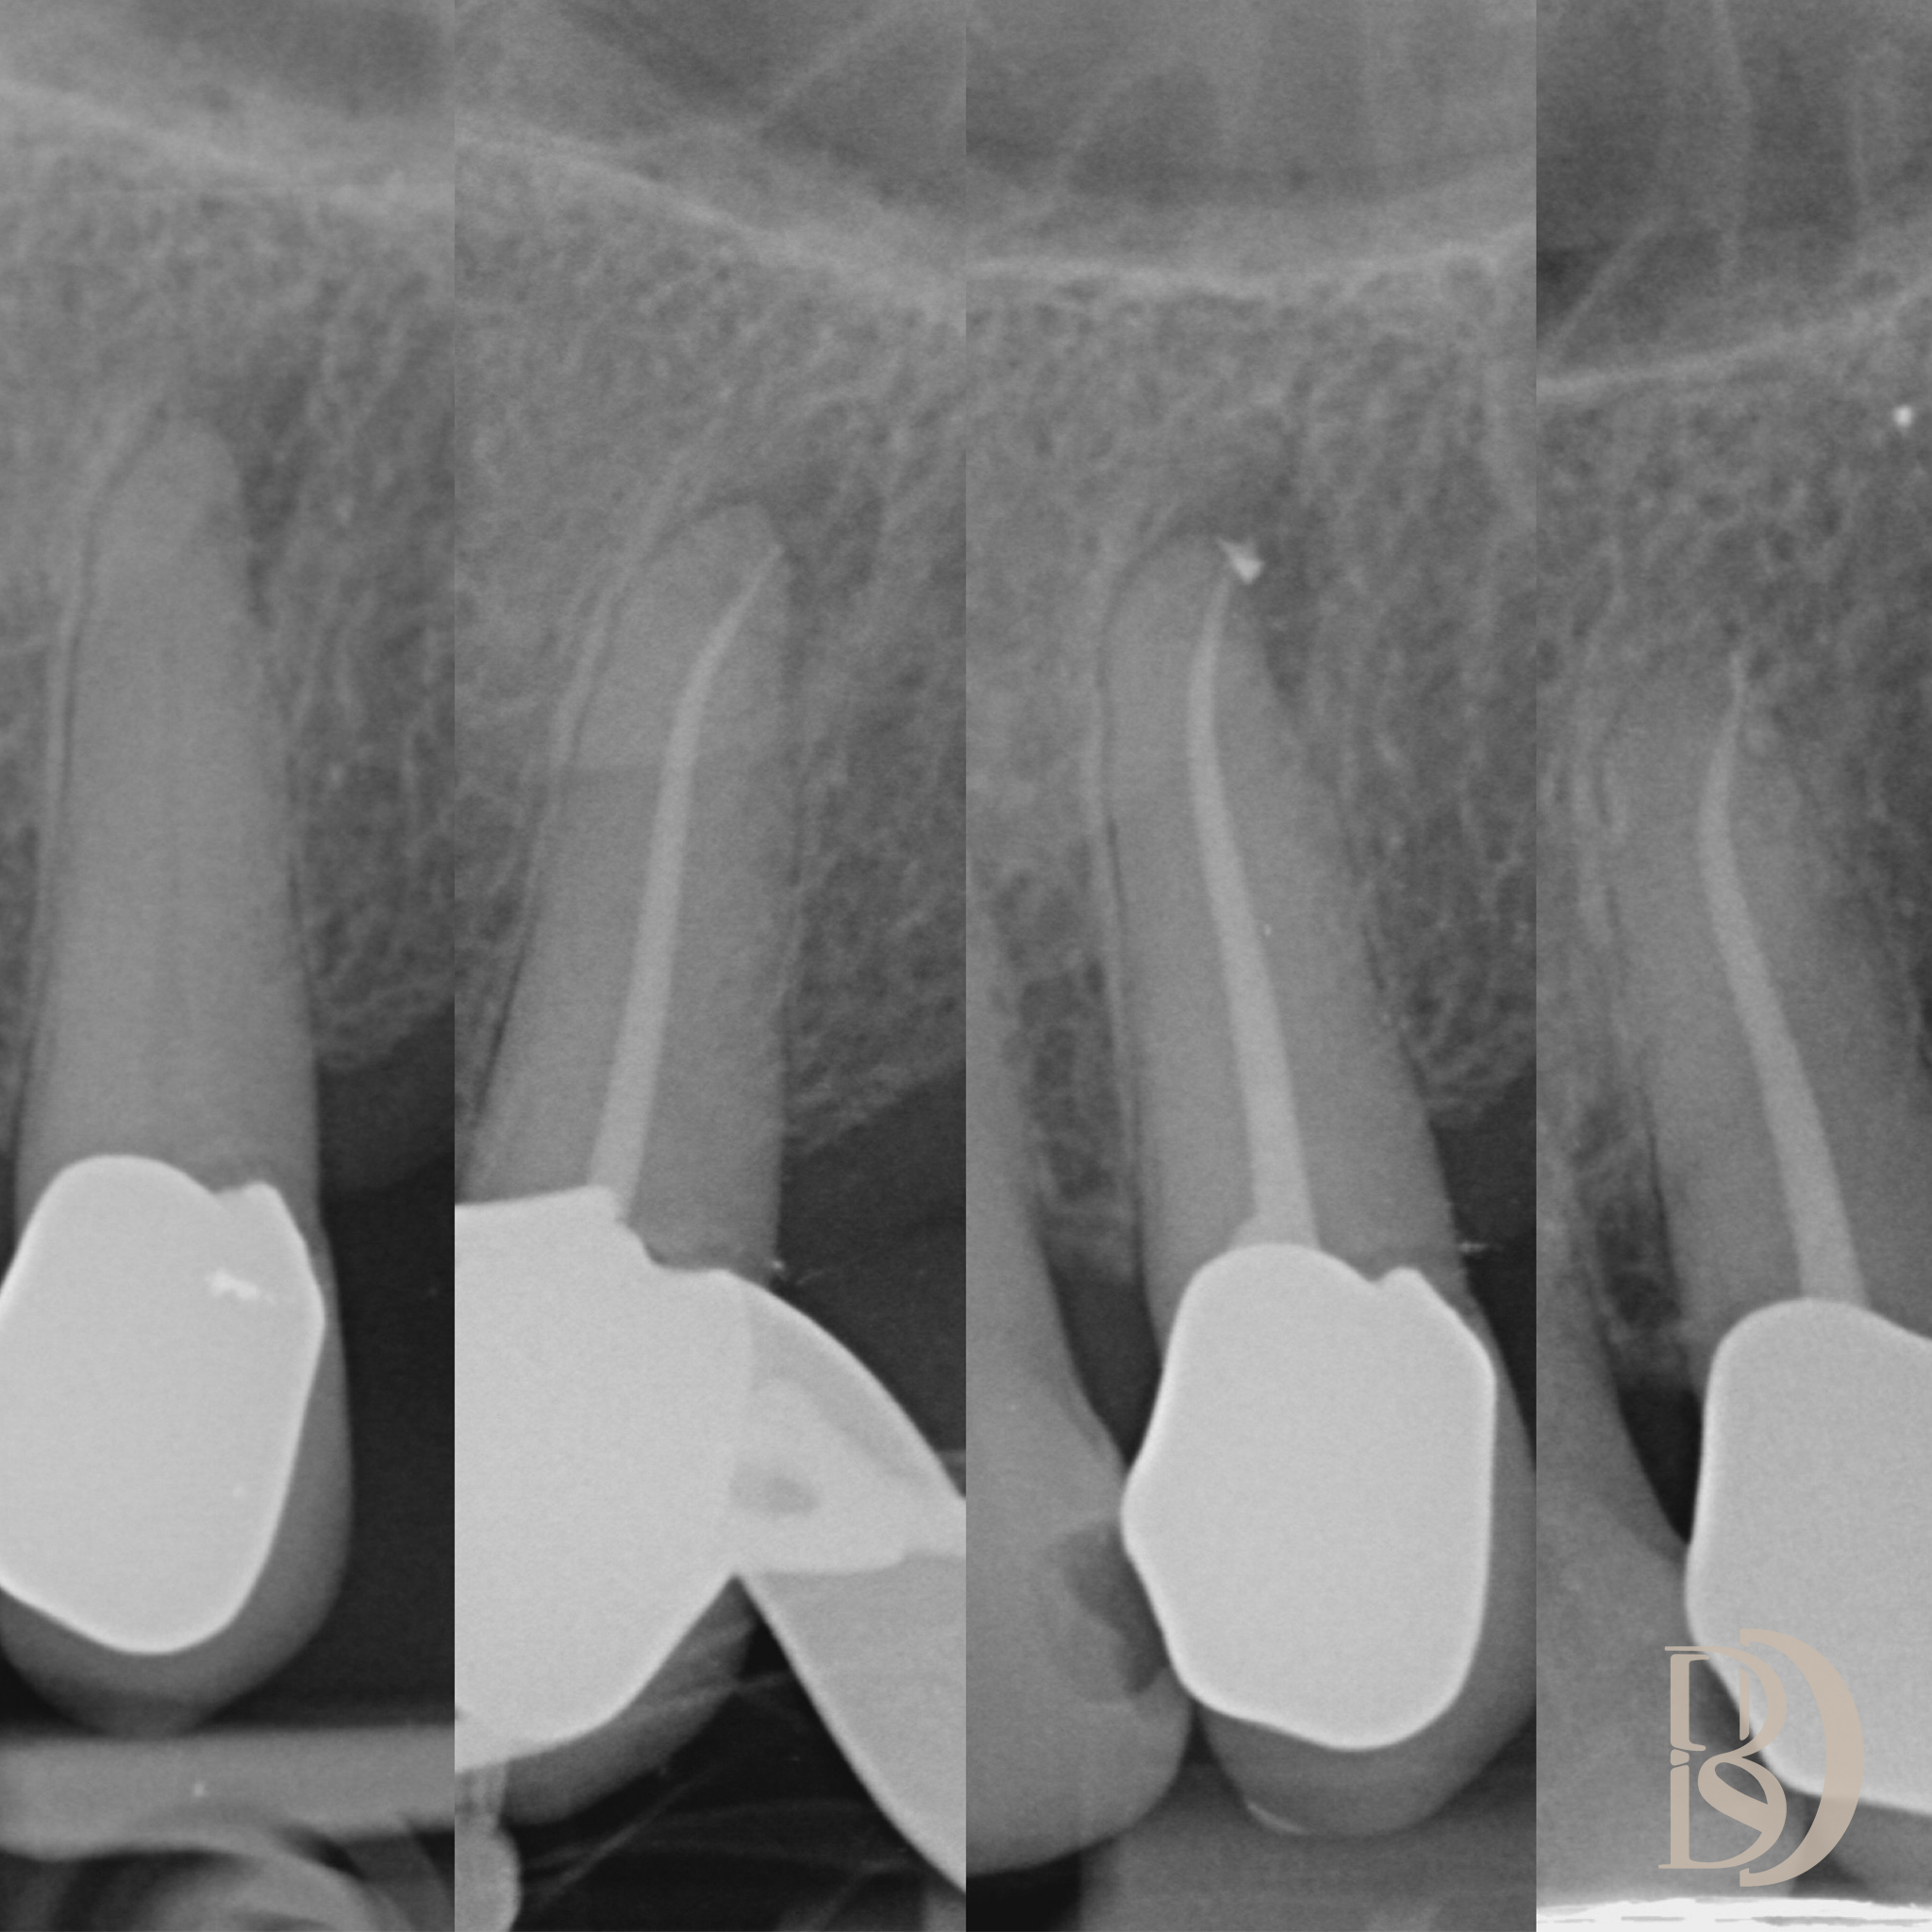

Some examples of Dr Fred’s Endodontic cases:

Dental X-ray showing multiple teeth, including root canal treatment on molars.